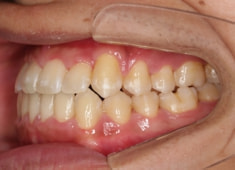

治療後(2年1ヶ月後)

下顎の右側への偏位は解消されました。

大臼歯は整直されております。

歯根のパラレリングは良好です。

左上2番の歯根も問題なさそうです。

下顎8番は保定期間に入り、しばらくして咬合が安定してから抜歯する予定です。

特に左側の咬合時の顎関節の位置に改善が認められます。